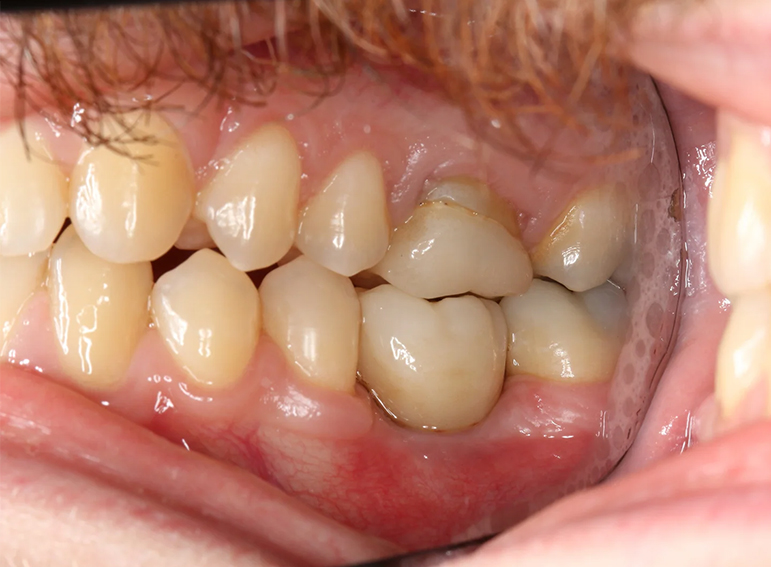

Implant to replace a molar with external cervical resorption.